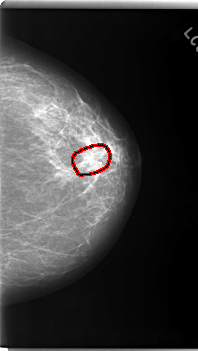

C_0170_1.LEFT_CC

FILE: C_0170_1.LEFT_CC.OVERLAY

TOTAL_ABNORMALITIES 1

ABNORMALITY 1

LESION_TYPE MASS SHAPE ARCHITECTURAL_DISTORTION MARGINS SPICULATED

ASSESSMENT 5

SUBTLETY 5

PATHOLOGY MALIGNANT

TOTAL_OUTLINES 1

BOUNDARY